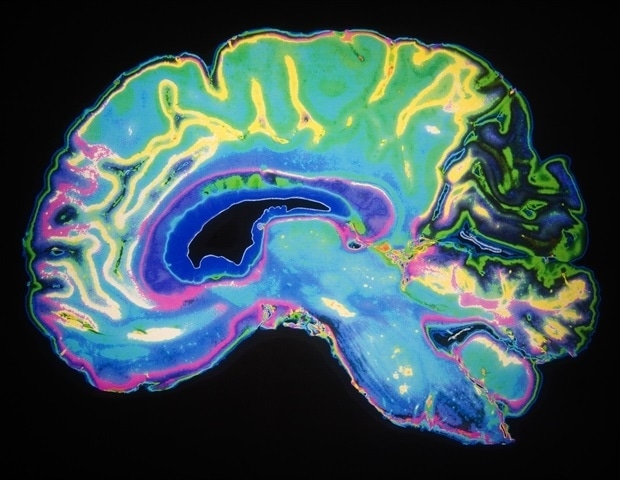

Эти функции связаны с частями мозга, где чаще всего возникают медленно растущие глиомы: в лобной доле, которая управляет поведением, личностью, суждениями и контролем импульсов, и в височной доле, которая контролирует слух, память, язык и эмоции.